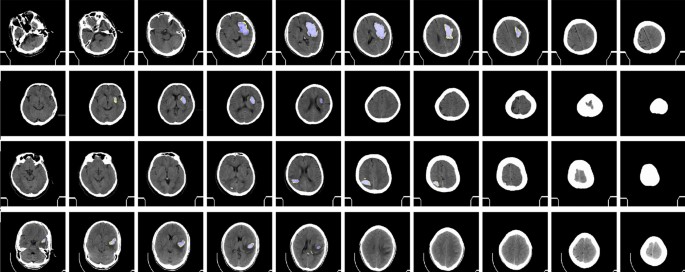

The quantitative output for ICH segmentation is shown in Fig. 4.

Samples of ICH segmentation prediction from GroupCapsNet and label hemorrhage region. (Best viewed in color and with zoom in).